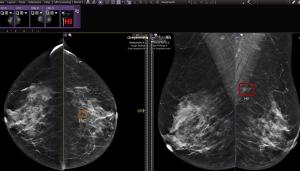

In a retrospective analysis of triennial screening mammograms for 134,217 women, a deep learning model offered comparable assessment of interval breast cancer risk across differences in age and breast density.

Noting an increased incidence of false negatives in screening and diagnostic mammography, researchers found that a personal history of breast cancer was associated with over a 3.6-fold higher likelihood of false negatives.

Pre-op breast MRI was associated with a 12.5 percent reduced 5-year cumulative incidence of recurrence for patients who underwent surgery for hormone receptor-negative cancer, according to newly published research.

In a recent interview, Deepa Sheth, M.D., discussed the rising incidence of breast cancer, key considerations in supplemental imaging for women with dense breasts and use of the CIVIE RadPod platform to facilitate consistent quality and imaging reads by fellowship-trained breast radiologists.